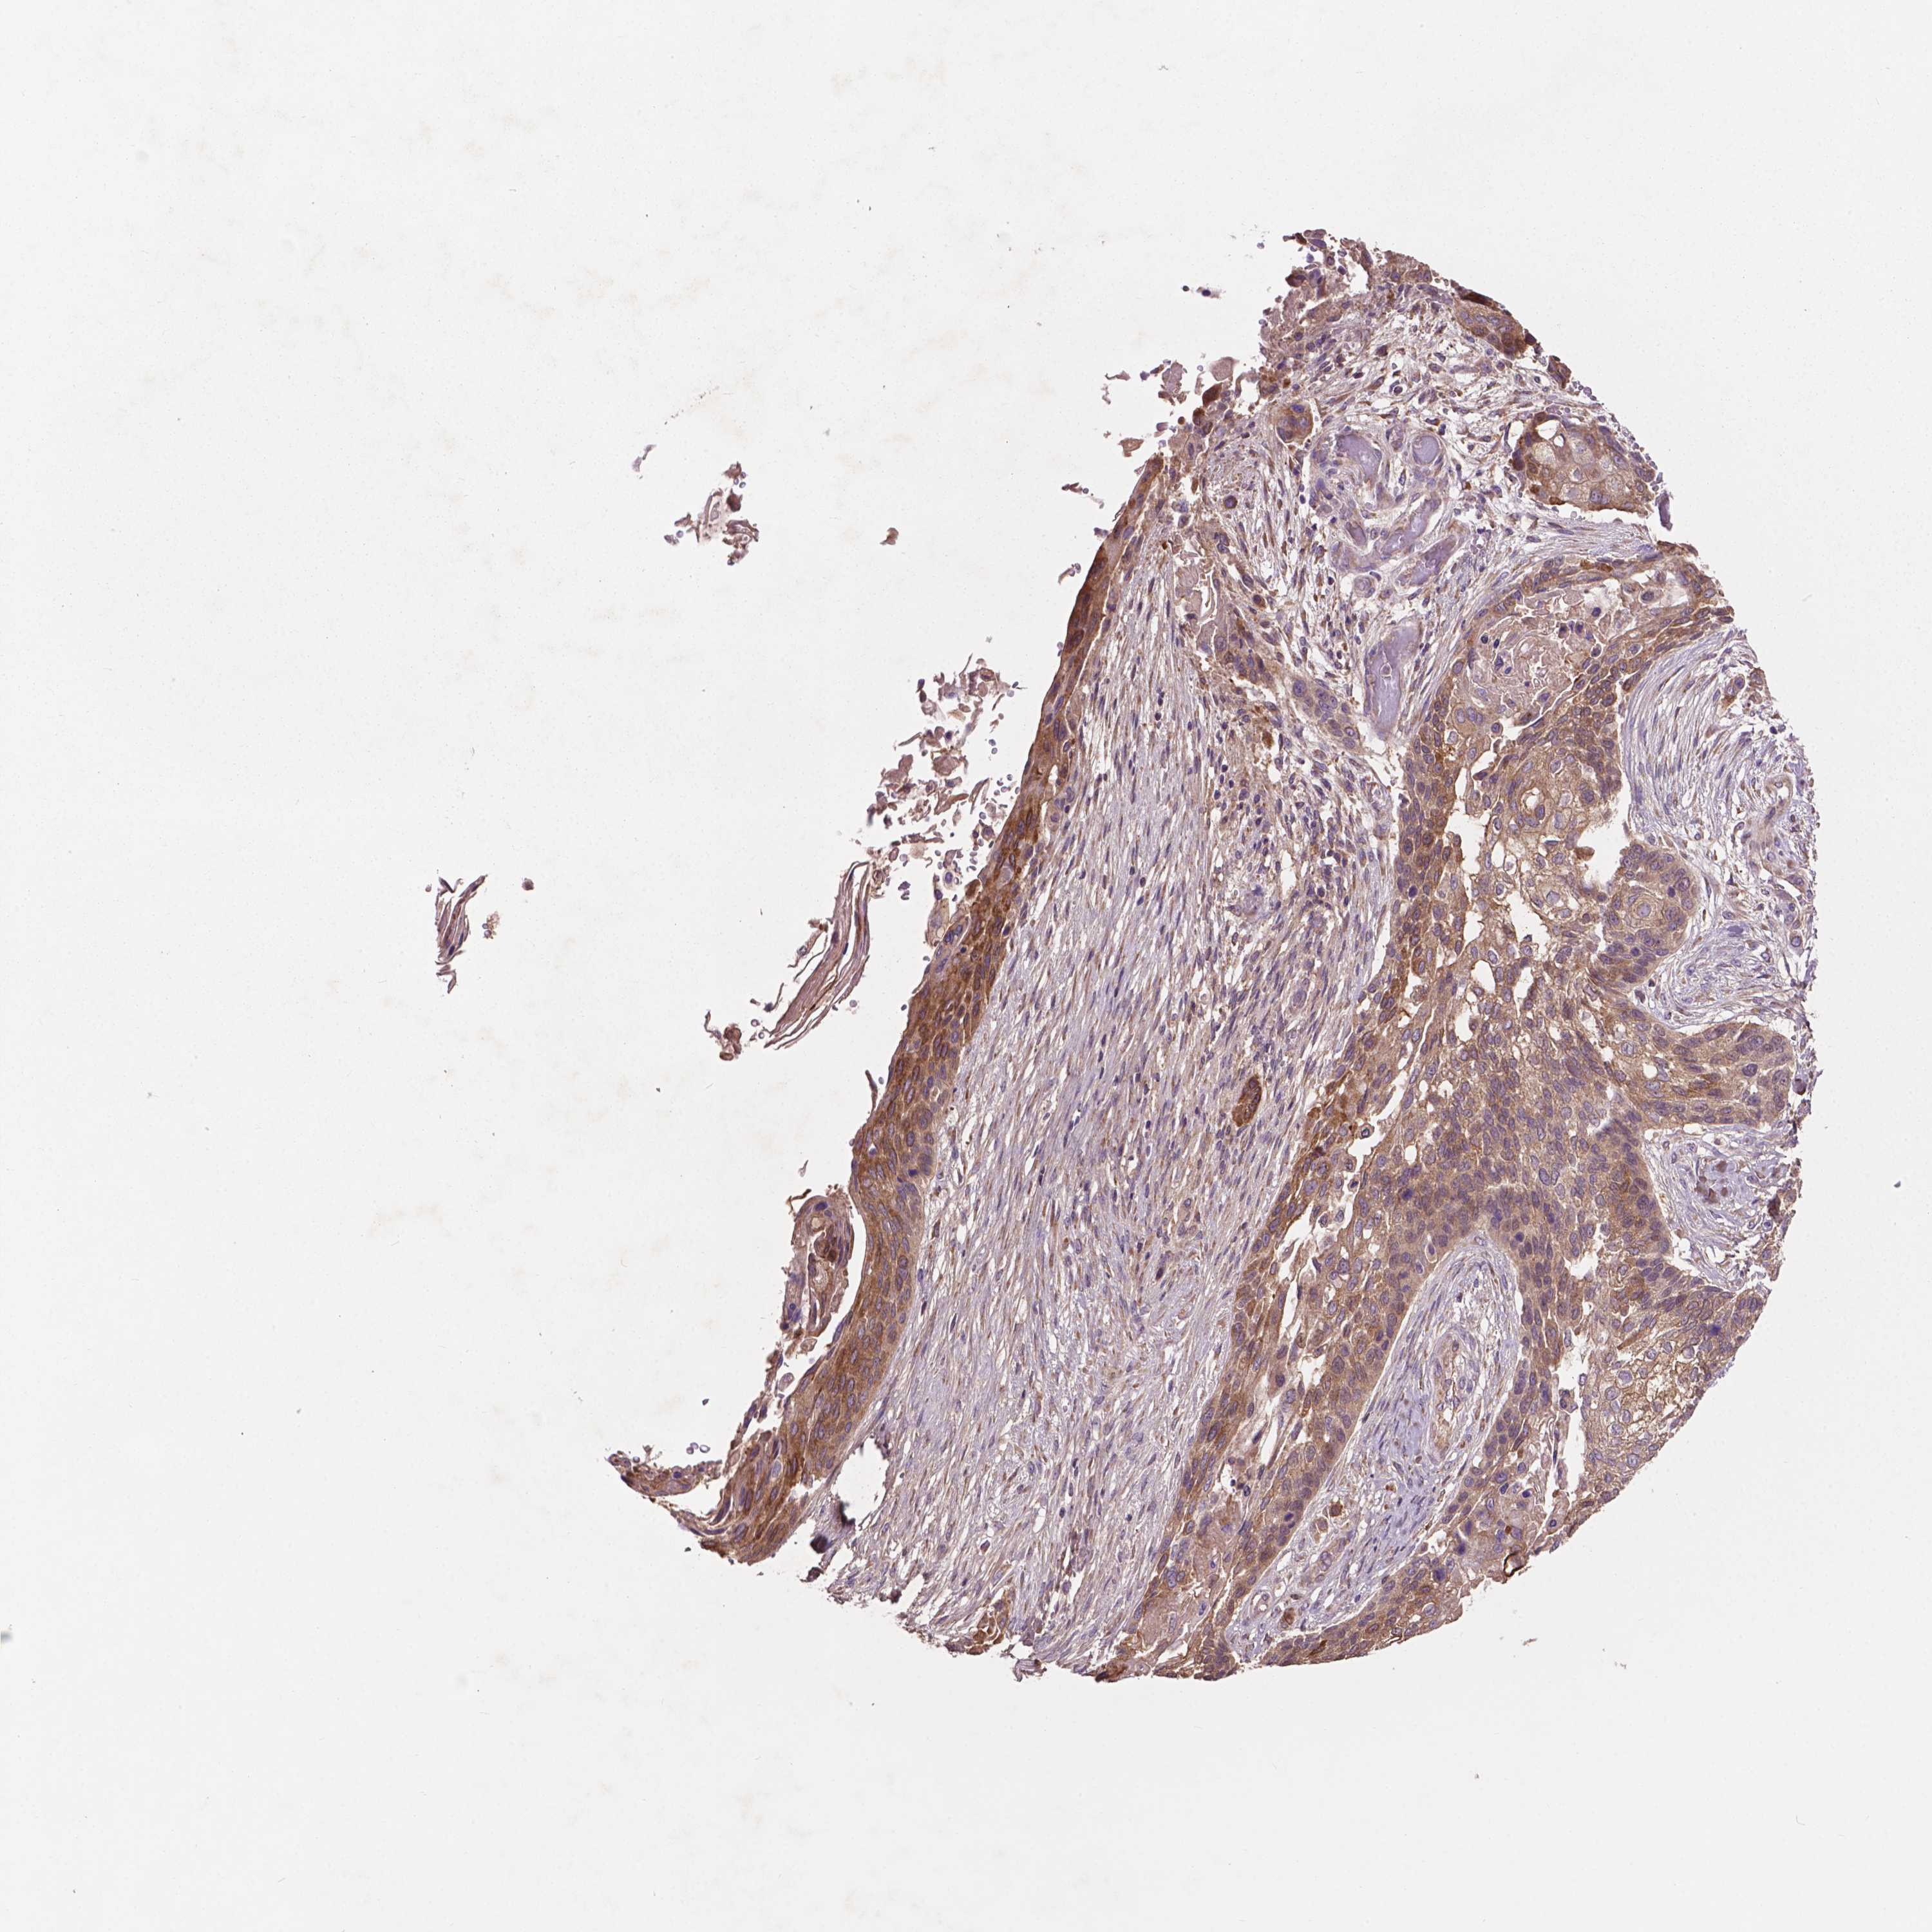

CANCER LUNG CANCER Show tissue menu